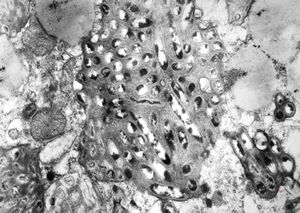

Whipple disease